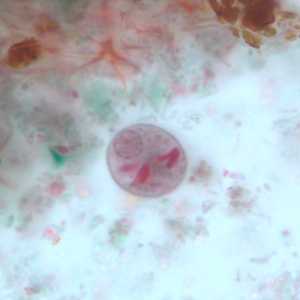

A 45-year-old pig farmer from rural Georgia presented to his health care provider with abdominal pain, cramps and diarrhea. Stool specimens were collected in polyvinyl alcohol (PVA) and 10% formalin for ova and parasite (O&P) examination. The objects in Figures A and B, which measured on average 90 micrometers in length, were observed in low numbers in formalin-concentrated wet mounts of the stool. The objects in Figures C and D, which measured on average 12 micrometers in diameter, were seen in moderate numbers on trichrome-stained slides prepared from the PVA-preserved stool. What is your diagnosis? Based on what criteria?

Figure B

This was a case of balantidiasis, caused by Balantidium coli (Figures A and B); also observed were cysts of Entamoeba polecki (Figures C and D). Diagnostic features included:

- ciliated trophozoites of B. coli (Figures A and B) containing a cytosome and macronucleus, and within the size range (40-200 micrometers) of the species.